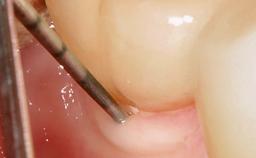

Mauricio Araujo and Flauvia Matarazzo present this straightforward clinical case, demonstrating the potential effect of implant placement depth on the resolution of peri-implant treatment. A 42-year-old systemically healthy female patient, a non-smoker with no history of periodontitis, was treated at the Dental Clinic at the State University of Maringá, Brazil between 2008 and 2009, when she received five implants restored with single crowns at sites 14, 26, 27, 36, and 46. After delivery of the implant-supported prosthetic restorations, the patient was enrolled in the supportive peri-implant therapy (SPiT) maintenance program at the same university.